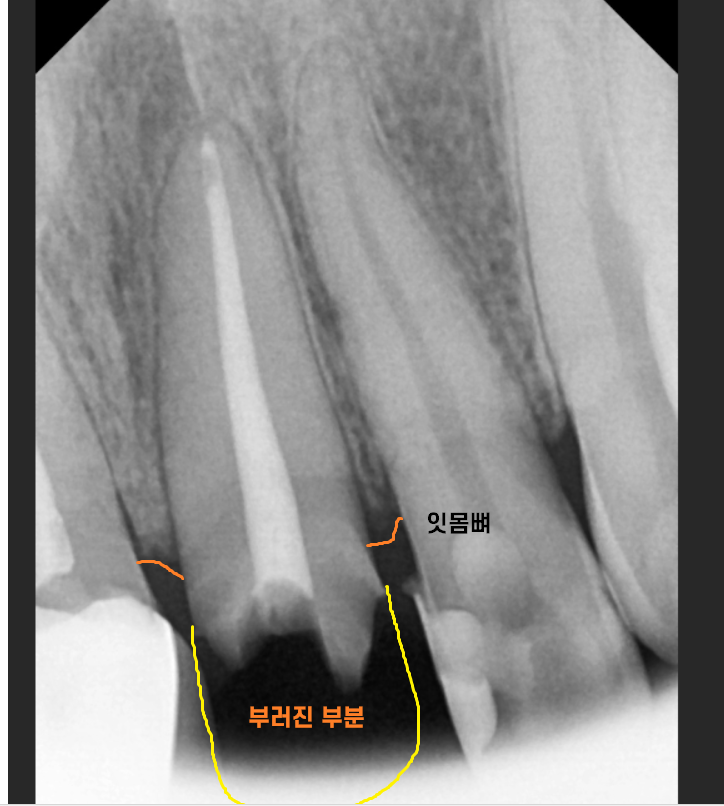

작은 x-ray로 한 번 더 확인해 보았습니다.

2/3 이상 머리가 없어졌네요..

앞니 부러짐 치료의 방향을 결정할 때에는

남아있는 치아의 양이 중요합니다.

살릴 수 있을지 없을지

예후를 결정하는

key point이죠!!

잇몸뼈에 뿌리만 박혀있는 수준이라

발치 후 임플란트 계획을

잡아드렸습니다.